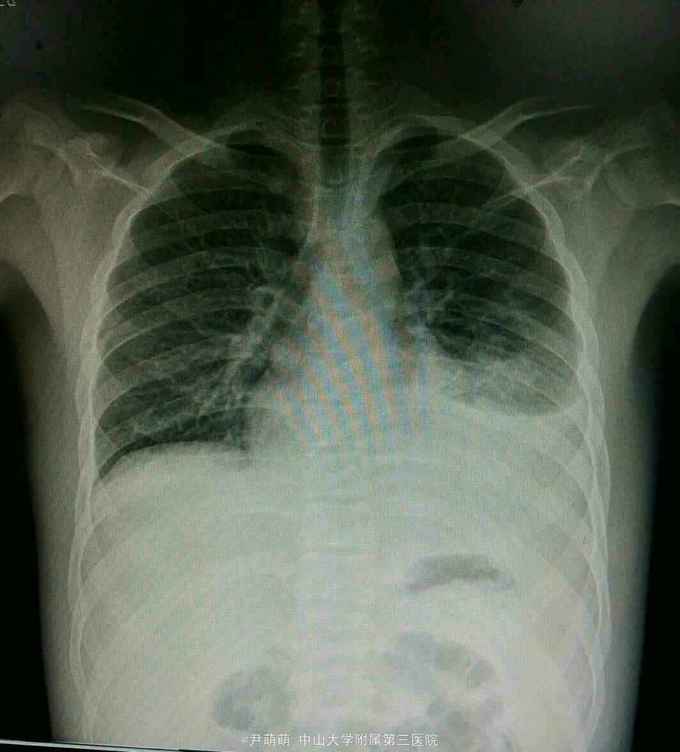

1、青年男性,急性起病,1月前曾有上呼吸道感染史。 2、患者11天前出现双下肢、颈部及腹部水肿,伴尿中大量泡沫,5天前出现发热咳嗽、咳痰,急查尿蛋白++,血白蛋白下降,胸片示左胸腔积液,左肺炎症,为求进一步诊治,遂入我院。

体查:T37℃,P90次/分,R:20次/分,BP:107/90mmHg 腹肌紧张,双下肢中度凹陷性水肿。

诊断:肾病综合征 肺部感染 治疗:人白蛋白 阿托伐汀 抗生素抗感染